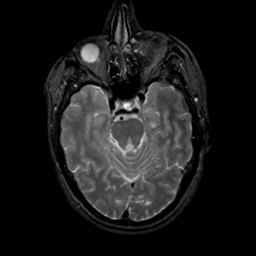

MR Study #17, July 7, 1991 -- Slice #17